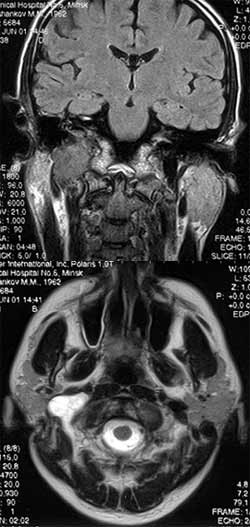

Лучевая диагностика опухолей височной кости.

Рис. 3. МРТ. Опухоль яремного отверстия справа.

Новости лучевой диагностики 2002 1-2: 28-29